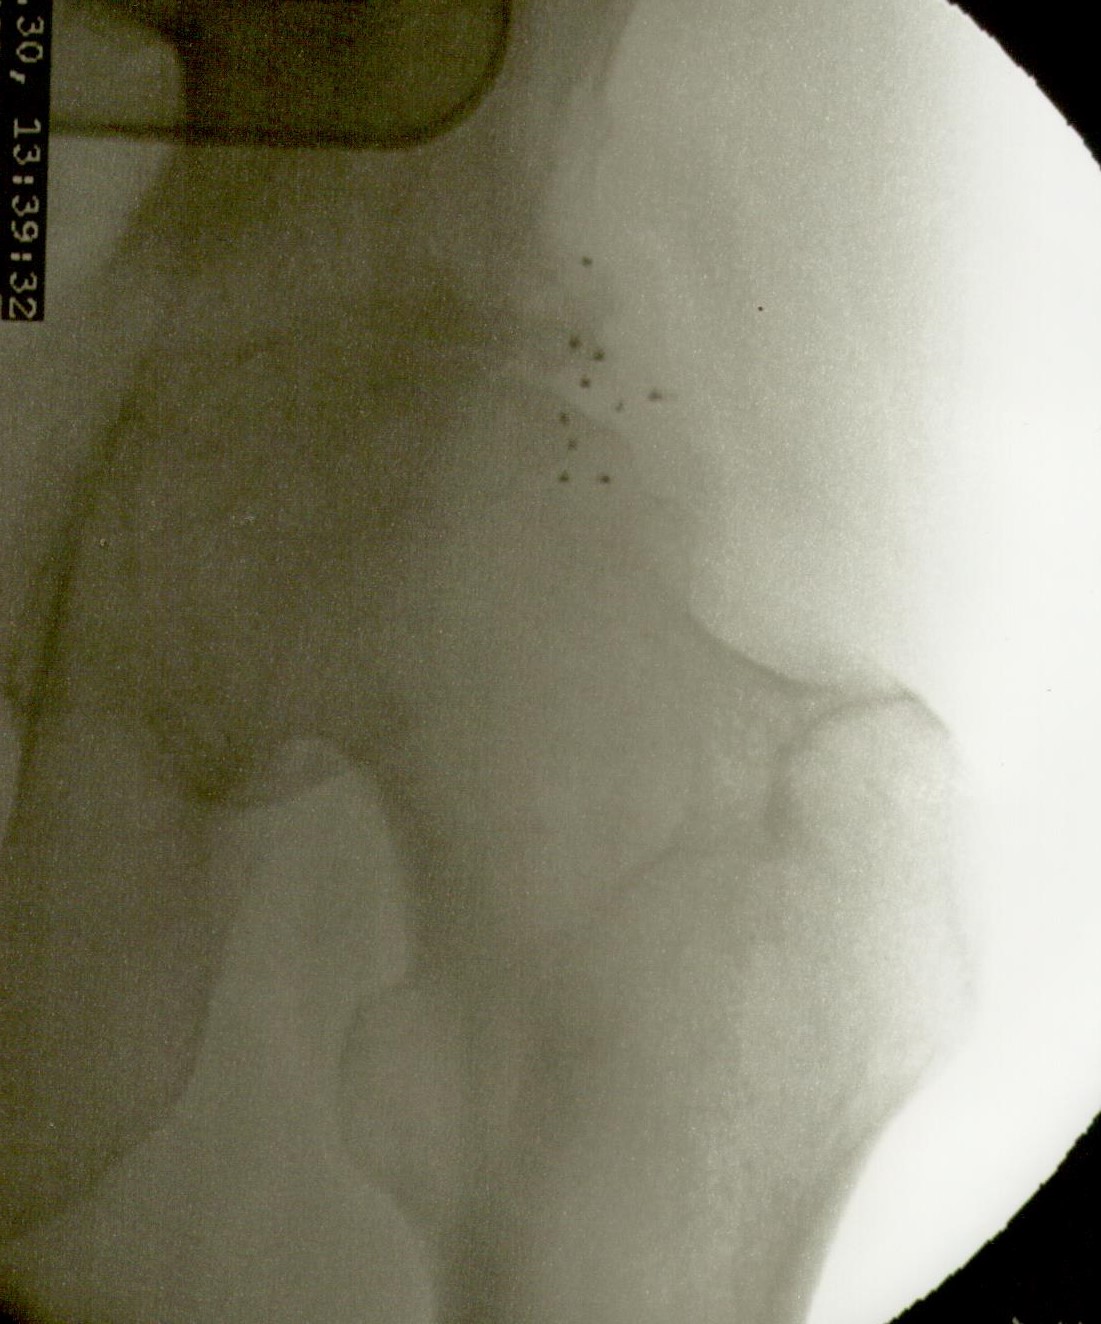

La artroplastia total de cadera para los casos de coxartrosis severa es el tratamiento de elección de la gran mayoría de cirujanos ortopédicos. Sin embargo cuando el paciente es menor de 50 años suele diferirse la intervención debido al tiempo de sobrevida del material protésico. También lo es en pacientes con deterioro del estado general debido a la avanzada edad o a enfermedades concomitantes (cardiópatas, por ej.) En estos casos la colocación de microimplantes de oro periarticulares alrededor del cuadrante súpero externo de la articulación es, habida cuenta del resultado sintomático y funcional, el tratamiento más indicado. La fácil colocación mediante control radioscópico y la rapidez de la recuperación (inmediata) hacen que este procedimiento sea seguro y muy útil para la remisión del dolor y la rigidez. No necesita ingreso ya que es una cirugía ambulatoria, se efectúa con anestesia local, y el paciente sólo requiere reposo relativo en el día de la intervención. Los resultados mediatos son excelentes. La mejoría clínica aumenta con los meses debido a la difusión de las nanopartículas de oro, por lo que contrariamente a los tratamientos convencionales que disminuyen su efecto con el tiempo, los microimplantes de oro lo mejoran. En cuanto esta técnica se popularice se reducirá significativamente el número de artroplastias.

Más abajo se observarán unas imágenes de casos de implantes de oro en cadera